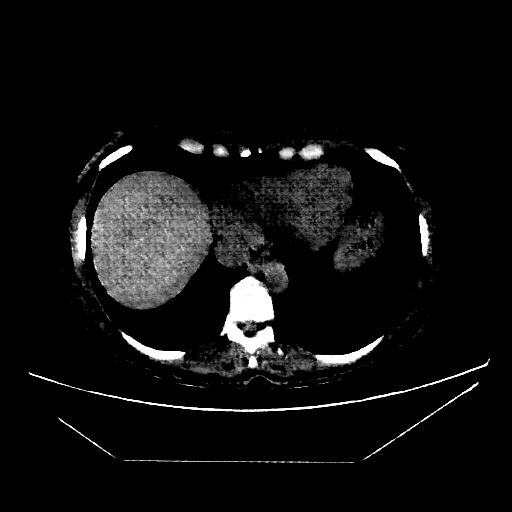

Image Grid

4Γ—3 grid: Rows show different image types (Original NATIVE, Reconstructed NATIVE, Original VENOUS, Generated VENOUS), Columns show windowing techniques (No Window, Lung Window, Mediastinum Window)

Original NATIVE CT scan (input)

Full window (WL 1023.5, WW 4095 β†’ Low βˆ’1024, High +3071)

Actual HU range: [-160.0, 240.0]